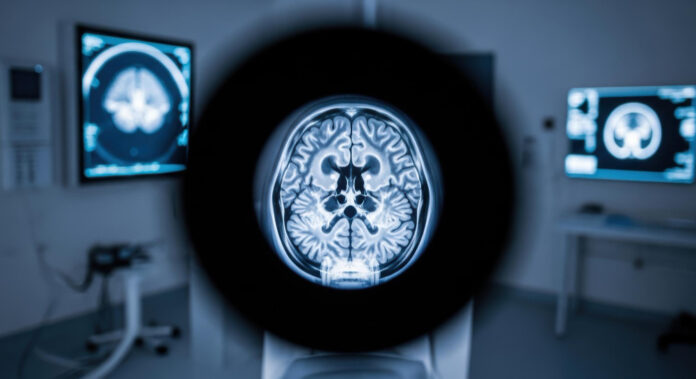

Tomografia computerizată (CT) este o tehnică imagistică care utilizează raze X pentru a crea secțiuni transversale ale creierului. Aceste imagini sunt apoi reconstruitе digital, permițând medicului să vizualizeze structuri interne, să identifice sângerări, fracturi craniene, tumori sau alte anomalii. În comparație cu alte metode, CT-ul oferă un raport excelent între rapiditate și claritate, fiind ideal în situații de urgență.

Prin imagini axiale, coronoane și sagitale, CT-ul permite identificarea:

- Sângerărilor – hiperdensitatea caracteristică a sângelui.

- Edemului cerebral – zone hipodense ce indică acumularea de lichid.

- Fracturilor craniene – liniile radiolucente în osul cranian.

- Leziunilor ischemice timpurii – zone cu densitate redusă în primele ore de la accidentul vascular cerebral.